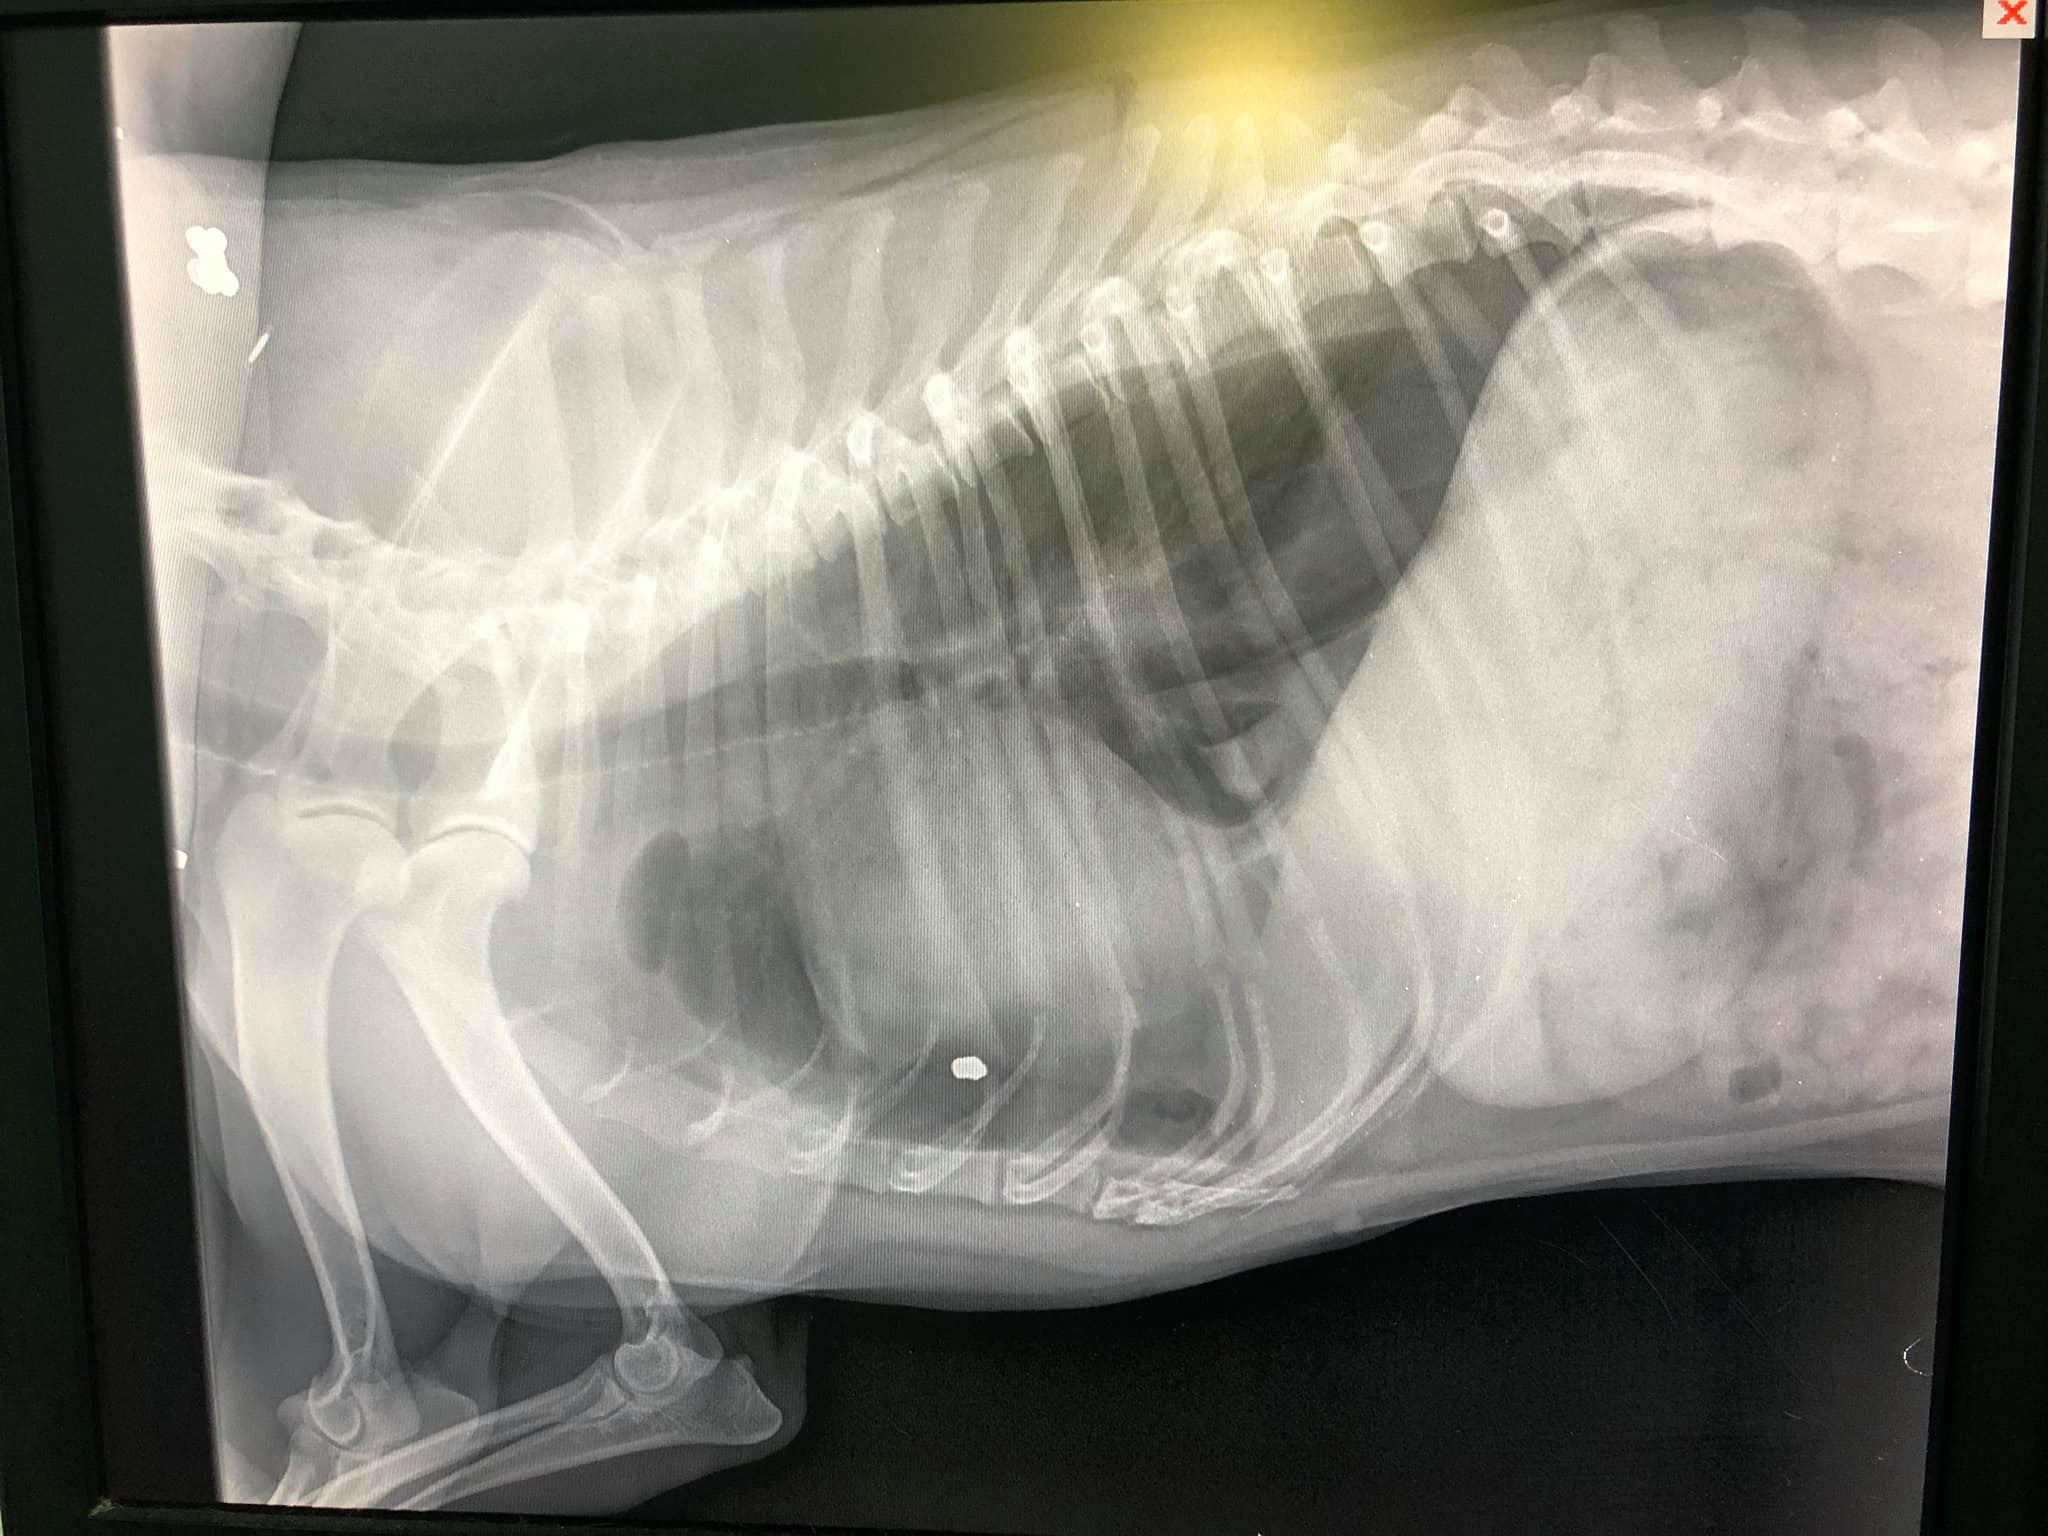

Στην κτηνιατρική κλινική του Νίκου Γαρμπή στην Καλλιθέα της Αττικής νοσηλεύεται σε κρίσιμη κατάσταση ο σκύλος που ξημερώματα εντοπίστηκε να βαριανασαίνει στην αυλή του σπιτιού του στον Πειραιά στη διασταύρωση των οδών Γυθείου και Αιγάλεω. Όπως έδειξε η ακτινογραφία το ζώο πυροβολήθηκε με αεροβόλο και το σφαιρίδιο πέτυχε τον σκύλο στον θώρακα, ανάμεσα στον πνεύμονα και την καρδιά.